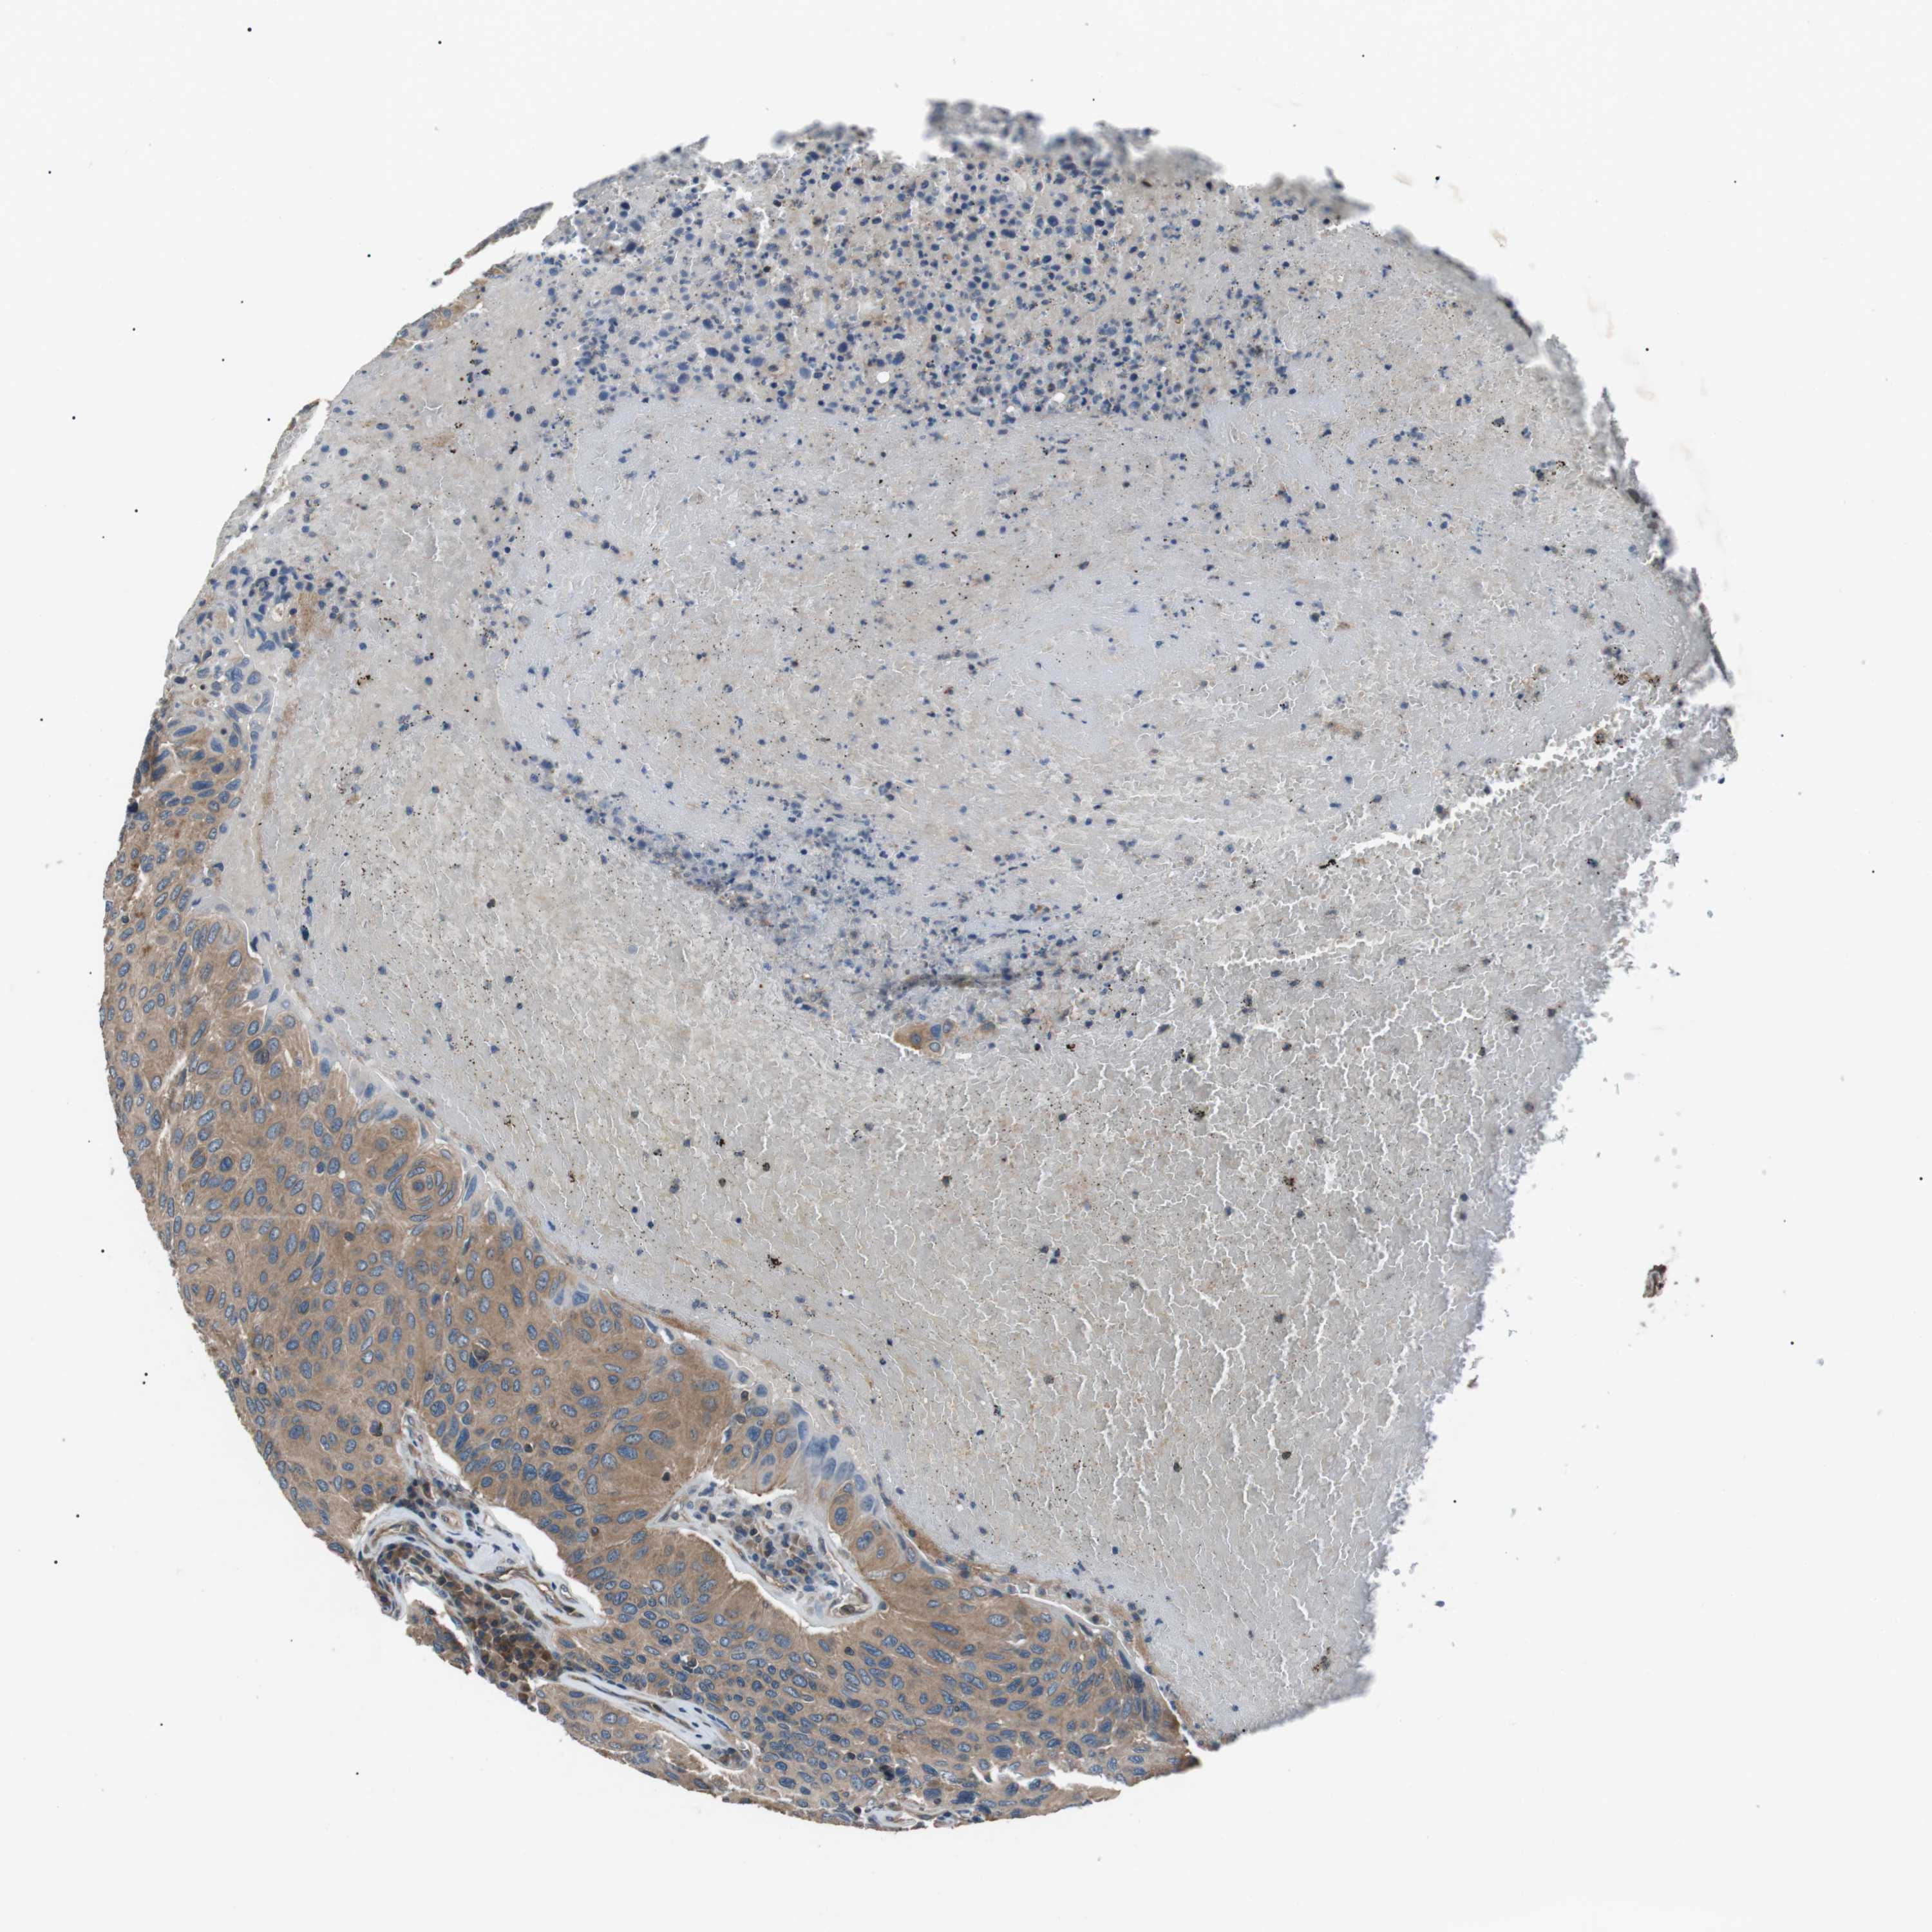

UROTHELIAL CANCER - Protein expressioni

A mouse-over function shows sample information and annotation data. Click on an image to view it in a full screen mode. Samples can be filtered based on level of antibody staining by selecting one or several of the following categories: high, medium, low and not detected. The assay and annotation is described here.

Note that samples used for immunohistochemistry by the Human Protein Atlas do not correspond to samples in the TCGA dataset.

Antibody stainingi

Antibody staining in the annotated cell types in the current human tissue is reported as not detected, low, medium, or high, based on conventional immunohistochemistry profiling in selected tissues. This score is based on the combination of the staining intensity and fraction of stained cells.

Each image is clickable and will lead to virtual microscopy that enables deeper exploration of all samples and also displays staining intensity scores, fraction scores and subcellular localization as well as patient and tissue information for each sample.

Antibody HPA015576

Staining

High

Medium

Low

Not detected

Intensity

Strong

Moderate

Weak

Negative

Quantity

>75%

75%-25%

<25%

None

Location

Nuclear

Cytoplasmic/membranous

Cytoplasmic/membranous,nuclear

Urothelial carcinoma, High grade

Urothelial carcinoma, Low grade